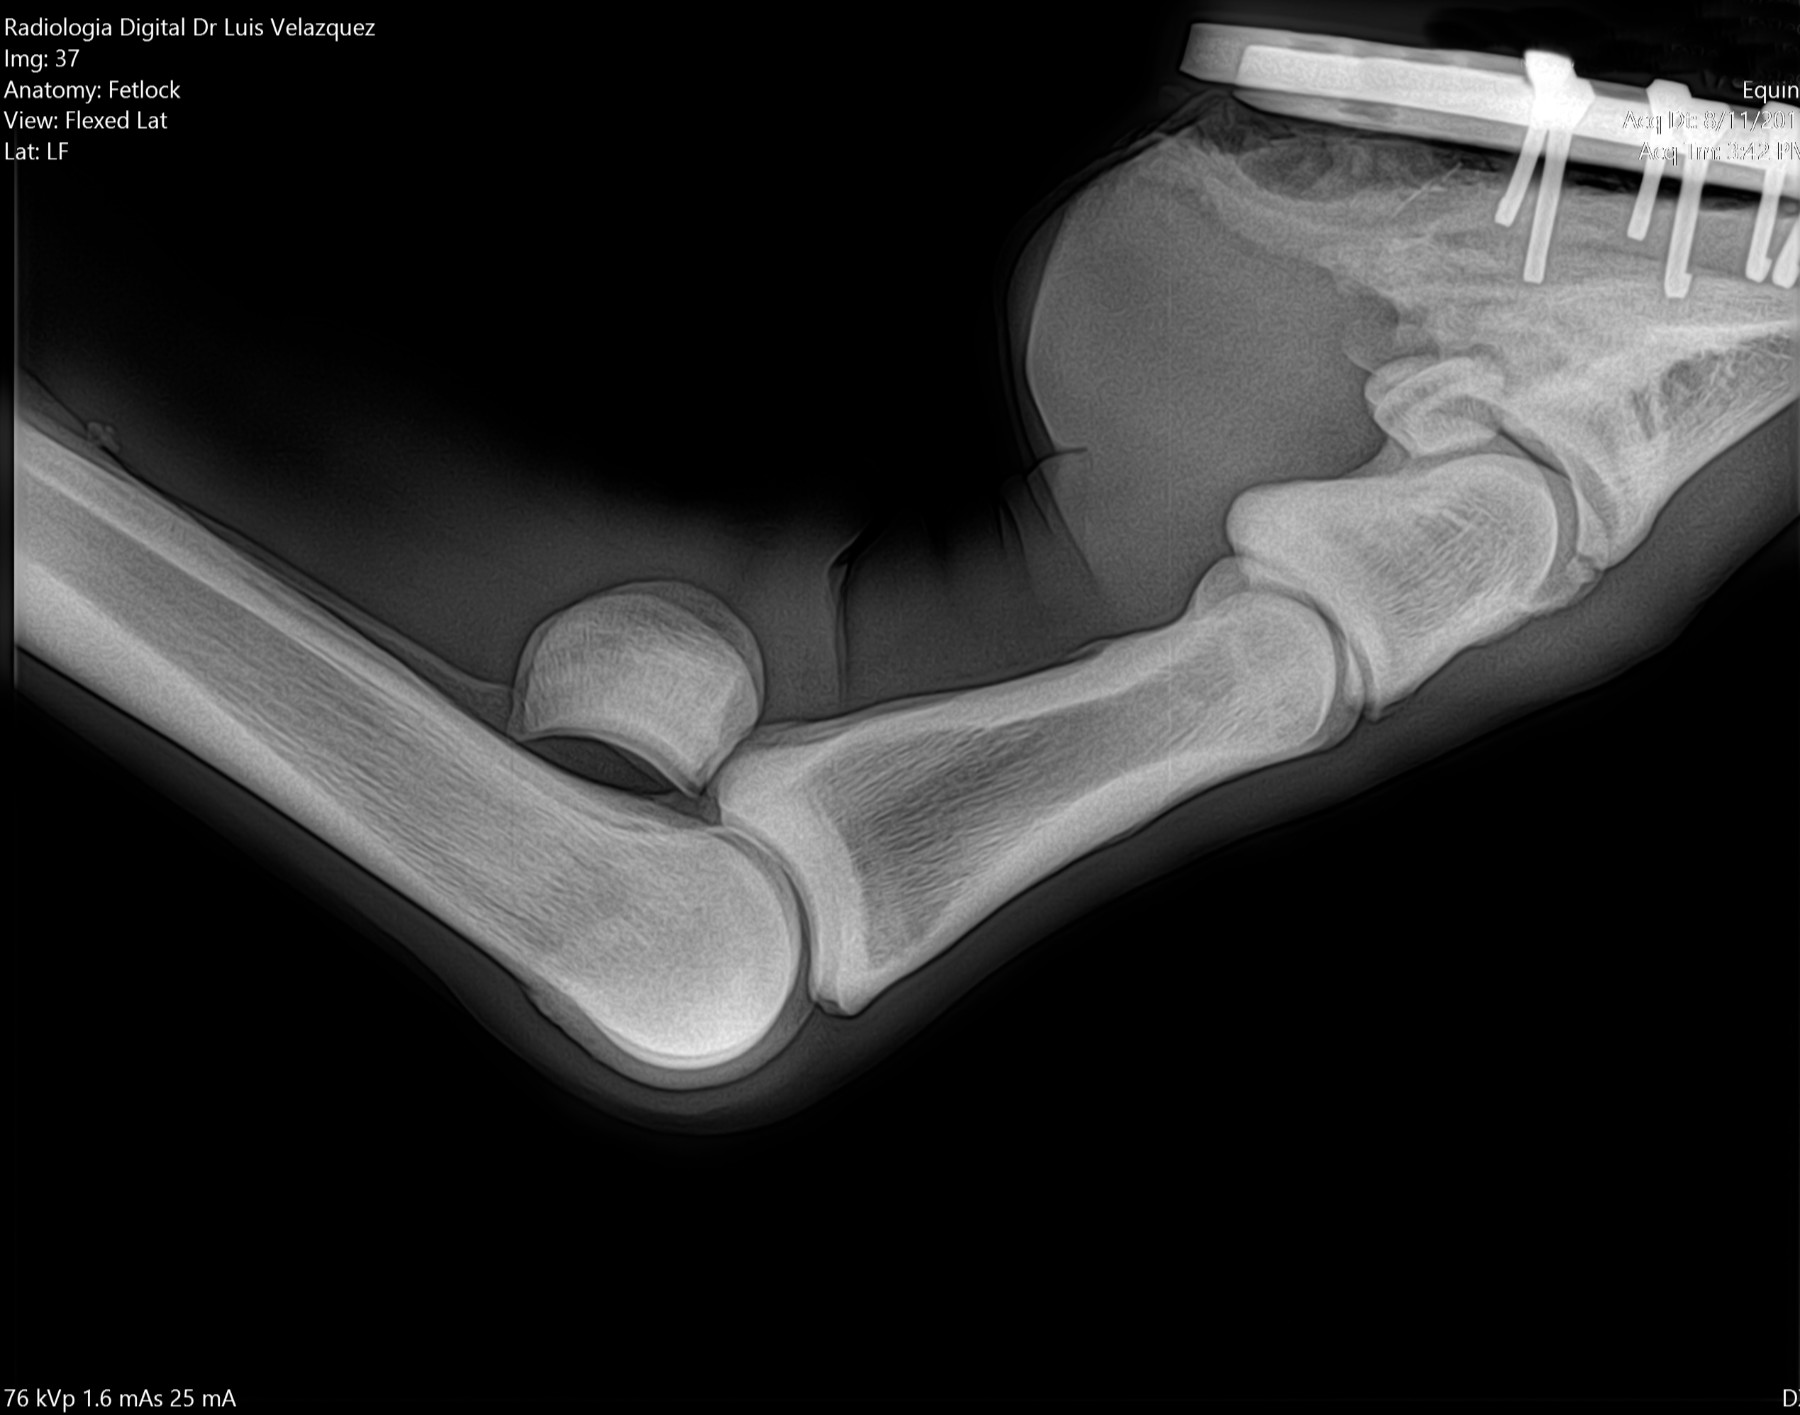

Radiología Digital como Herramienta Complementaria en el Dictamen de Bienes Muebles

Desde el descubrimiento de los rayos “X” y las placas radiográficas por Wilhelm Conrad Roentgen y su posterior difusión a través de la Asociación Físico médica de Wurzburg el 28 de diciembre de 1895, que fue la primera asociación que habló de los nuevos rayos que podían penetrar el cuerpo y fotografiar los huesos, ha habido muchos cambios tanto en la forma de obtener, procesar e incluso en la forma de visualizar, manejar y almacenar las placas radiográficas.